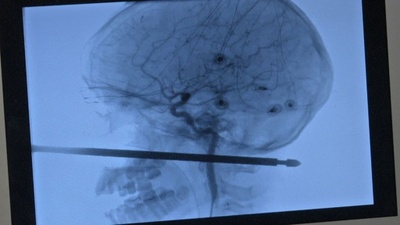

ツリーハウスから転落し金串が頭部ほぼ貫通、脳に損傷なし 米10歳児